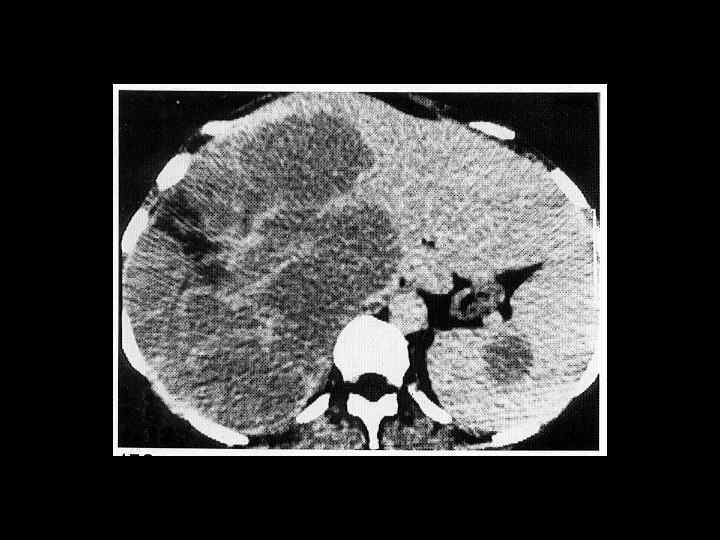

АКТУАЛЬНЫЕ ВОПРОСЫ РЕНТГЕНОЛОГИИ ЛУЧЕВАЯ ДИАГНОСТИКА ЗАБОЛЕВАНИЙ СЕЛЕЗЕНКИ Спленомегалия: Причины - Заболевания системы крови (гемолитические анемии, острые лейкозы, хронический миелоидный лейкоз, злокачественные лимфомы) - портальный цирроз печени - тромбоз селезеночной вены